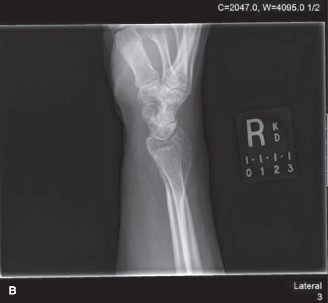

Radiographic Evaluation

Anteroposterior and lateral radiographs of the right knee demonstrated an eccentric, purely lytic lesion in the metadiaphyseal region of the distal femur, extending into the subchondral bone of the lateral femoral condyle. The lesion was expansile, with a narrow zone of transition, and showed no significant sclerotic rim, a classic radiographic hallmark of an active benign or low-grade malignant bone tumor. Cortical thinning and a pathological stress fracture line were noted along the lateral cortex. There was no evidence of periosteal reaction, Codman triangle, or internal matrix mineralization (no chondroid rings/arcs or osteoid cloudiness). The epiphyseal plate was noted to be completely fused, consistent with the patient's skeletal maturity.

Figure 1: Initial AP radiograph demonstrating an expansile lytic lesion in the distal femur, extending to the subchondral bone, with cortical thinning and lack of sclerotic margin.